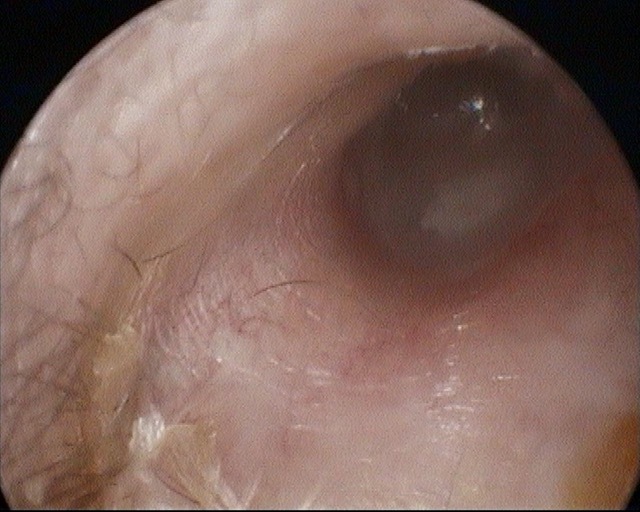

Perforation